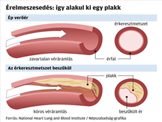

• Érelmeszesedés valóban elkerülhető, megakadályozható, visszafordítható?

Az érelmeszesedés nem jár együtt a korral – már huszonéveseknél is kialakulhat. Az érfalakban keletkező lerakódások és az érfalak merevvé válása nem időskori jelenség. Hol vannak az érelmeszesedés tipikus helyei? Az érelmeszesedés kialakulása.

Homocisztein káros hatása az érelmeszesedésre. Az érfal (endothelium) sérülésének oka. Az érfal (endothelium) sérülésének oka. Az egészséges endothel működésében központi szerepet játszik a nitrogén-monoxid (NO). Érelmeszesedés megelőzése, csökkentési lehetősége, kezelése. Rezveratrol, fokhagyma, Golden Yacca Plus, K2 vitamin kedvező hatása. Sztatin gyógyszer hatása az érelmeszesedésre.

Szintetikus gyógyszerek hatása. Érelmeszesedés megelőzése, csökkentési lehetősége, kezelése